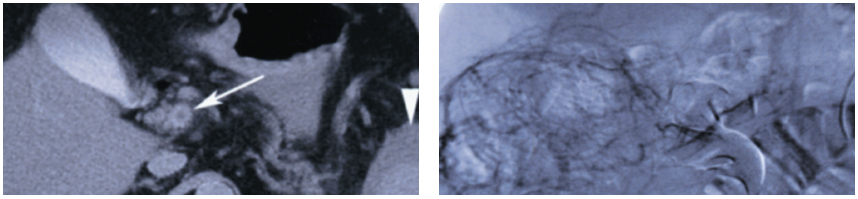

Repeated abdominal CT showed thrombosis of the superior mesenteric vein and fluid around the spleen (Figure 1). The thrombus extended into the portal vein. An abdominal angiogram demonstrated thrombosis of the superior mesenteric vein as well as diffuse venous collaterals, consistent with subacute mesenteric venous thrombosis (Figure 2).

Radiographic imaging confirms the presence of a thrombus. Plain films generally reveal nonspecific changes (such as dilated loops of bowel with air-fluid levels) and can show whether free air is present—a finding that mandates emergent surgical evaluation. Contrast-enhanced CT may demonstrate bowel wall thickening, pneumatosis intestinalis, and vascular occlusions.2,6 Magnetic resonance angiography (MRA) has evolved over the past few years and now rivals conventional angiography. It is possible to visualize the anatomy and determine patency as well as flow rates of the mesenteric arteries and veins with MRA; however, it is less useful in the evaluation of smaller or more distal mesenteric vasculature.6 Conventional angiography is helpful when the presence of thrombosis cannot be confirmed with noninvasive imaging modalities alone or when thrombolytic therapy is used.2,3,6,7